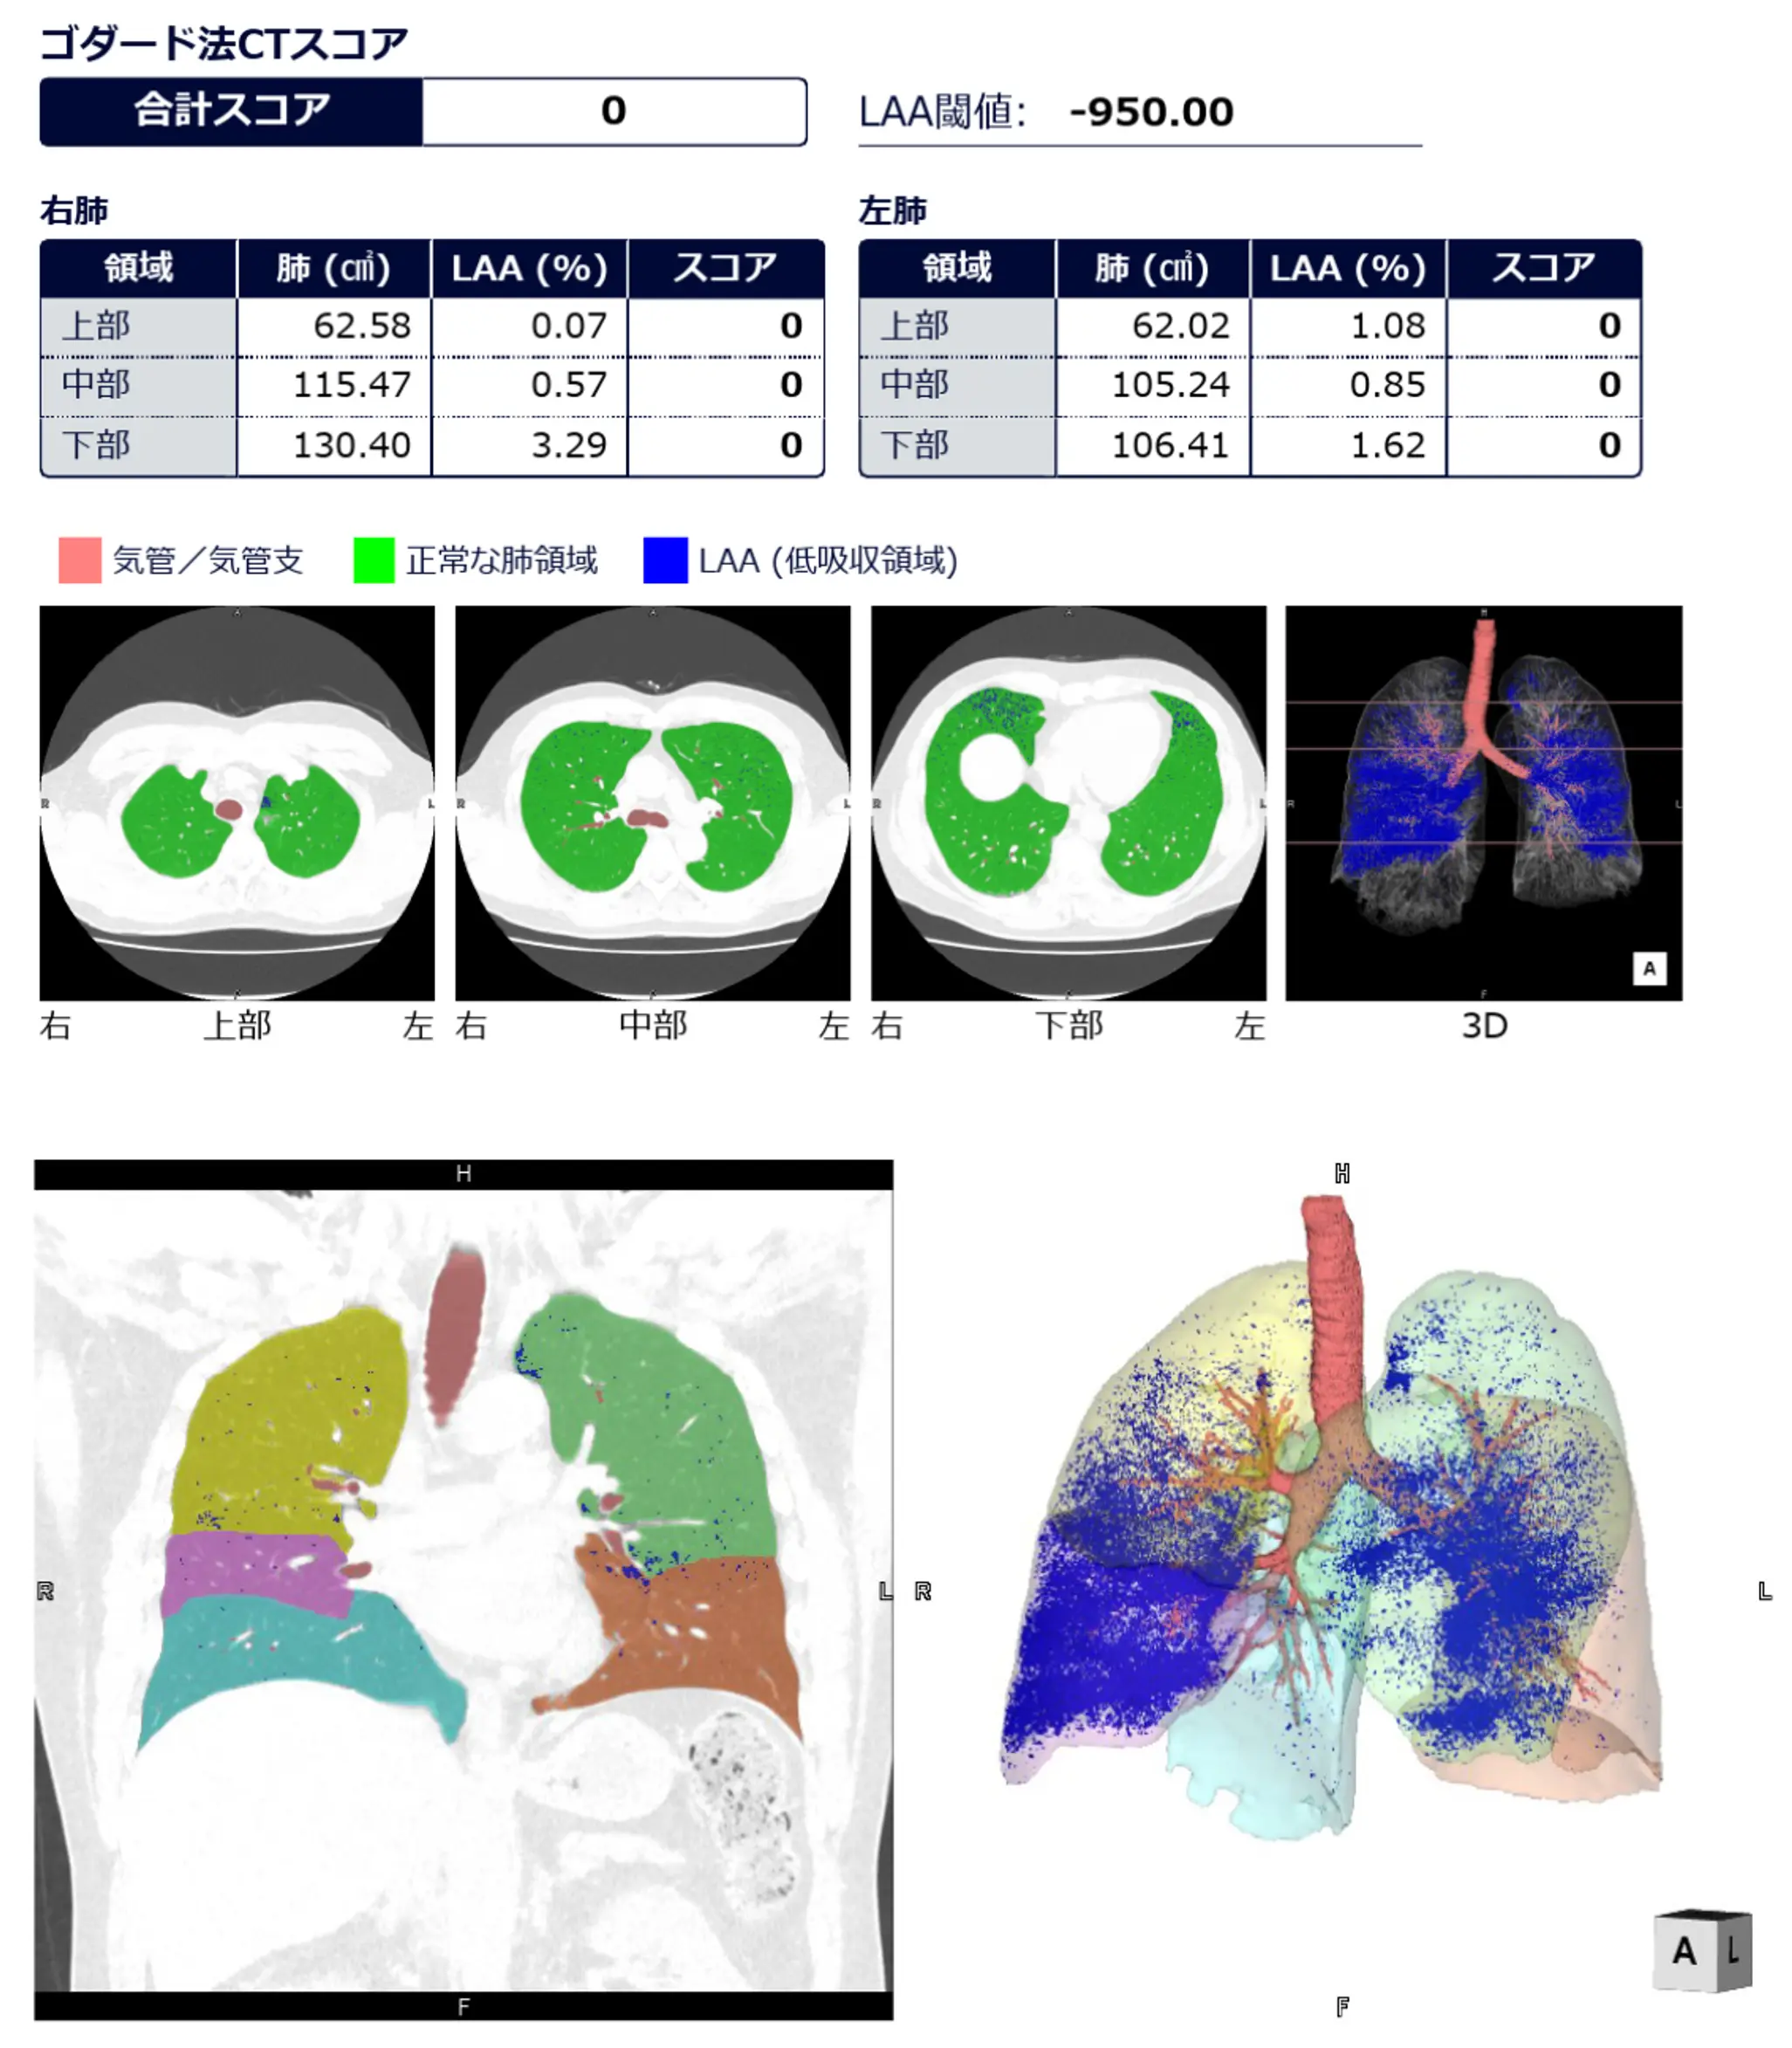

気腫性変化の定量解析レポート

全ての方を対象に、自然加齢や喫煙とともに生じる、肺のスカスカ化(気腫性変化)の3Dレポートもお渡しします。慢性閉塞性肺疾患(COPD)など、進行すると場合によっては重度の息切れや呼吸困難を引き起こす呼吸器疾患のリスクを予防・軽減する上で非常に重要です。